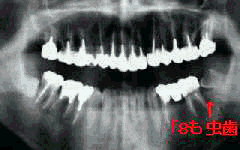

再初診時パノラマ写真 3年後パノラマ写真

26歳 男性 折角萠出した「8もまたムシ歯

口腔内およびX線所見:

度重なる治療と口腔衛生指導のおかげで、口腔内清掃状況は比較的良好ではあったが、 「8の大きなムシ歯がひときは目立つ感じがした。レントゲンを見るまでもなく 「8歯髄炎による疼痛であることがわかった。

8年前の初診時に、今時ここまでひどいムシ歯を作るかと感心しながら治療を始めたことが 思い出される。下顎の前歯を除いてほとんどの歯が抜髄を必要とする状態であった。 順次、抜髄を行って治療を進めて行ったが途中で中断。その4年後再び来院された時には、折角 抜髄した歯も治療中断のため使用不可能な状態になっていた。

特に「7の二次カリエスはひどく保存不可能な状態になっていたので「8の萠出を期待して抜歯。 さすがに本人も、「今回は懲りました、こんどこそまじめに治療します」と態度を改めて最後まで 治療を継続した。しかし、治療終了後は執拗なメインテナンスの説明にも関わらず足が遠のいた まま3年を経過して今回の来院となった。

処置は「8抜髄の上フルクラウンによる補綴。

使い物にならない水平埋伏歯の「8も、「7の抜歯により機能するまでに萠出することを 期待しての処置も、再びムシ歯により夢が砕かれた状態である。 カリエスの管理がもっと為されていれば期待通りの効果が得られたようにも思われる。